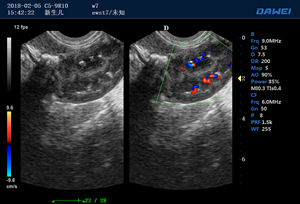

·支持B、C、PW、CW、寬景成像

·實時空間復合成像